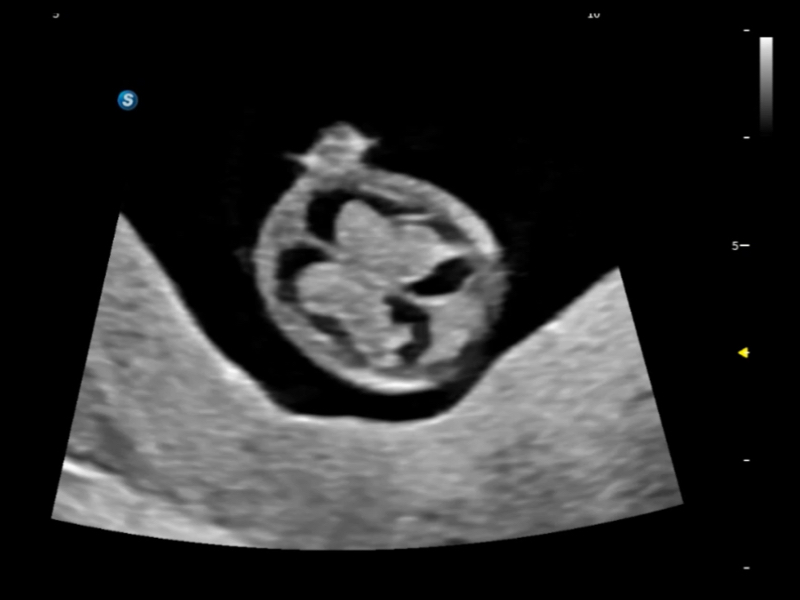

S80 提供多樣化超聲成像技術(shù),可滿足不同科室的需求,在助力掃查診斷和介入治療中發(fā)揮著重要作用。